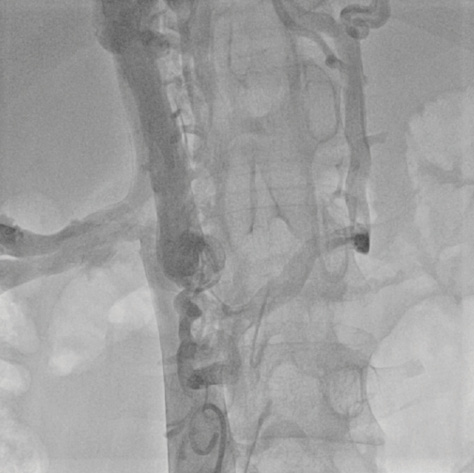

Coronary angiography showed multiple fistulas between the inferior vena cava and the pulmonary veins/left atrium (Figure 2). Three of those veins were embolized by implanting Amplatzer plugs (10-mm Plug II, 12-mm Plug II, 6-mm Plug IV) (Figure 3). After a 3-hour procedure, it was decided to stop and to postpone further treatment of the other fistulas. Her systemic oxygen saturation had increased to 88%. However, the patient still experienced palpitations, facial flush, and sporadic events of systemic arterial hypertension. Furthermore, events of hemoptysis and acute dyspnea occurred.

Figure 3. Fluoroscopy in the anteroposterior view showing implantation of a 10-mm Amplatzer vascular plug II.